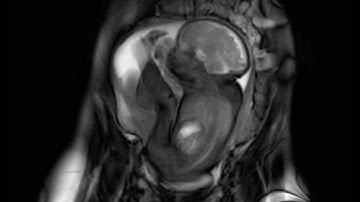

MRI scan at 32 weeks